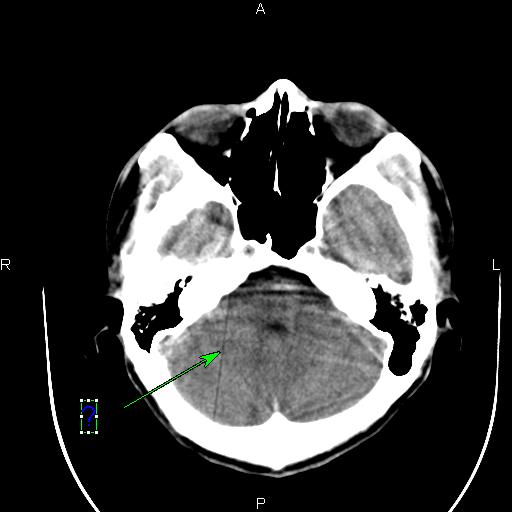

[设备故障求助] 东软ct图像伪影求助

B13F_001.jpg B13E_001.jpg B141_001.jpg B140_001.jpg

这种伪影是怎样造成的?怎样解决呢?

应该是某个通道跳起引起的直线伪影。你可以在过滤成像里检查一下,应该可以看到一跟亮线,找到是某个通道,然后屏蔽就可以了。另外一种方法就是,在ps里,不放线,不旋转,之间看所有的通道值,有没有跳起的?在ps里,放线,不旋转,这样可以看得更加清晰!你可以找到跳起的通道,或你也可以找到相应位置的das板,然后把有问题的das板换到边上,这样也可以解决问题。应该是检测器中间部位的某个das板或是通道引起的伪影